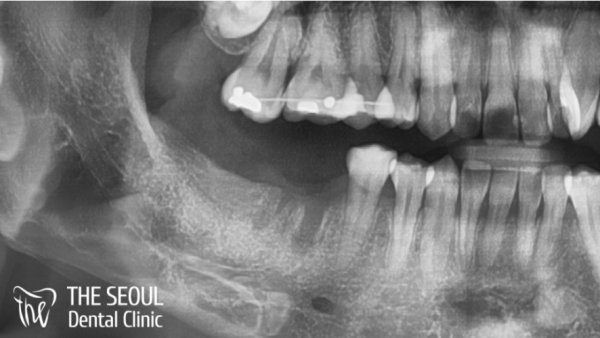

이 외국인 환자분은 오른쪽 어금니 두곳이 빠진채로 있어서

이부분에 대한 임플란트를 진행하고 싶어하셨답니다.

발치의 흔적이 아물지 않은것이 그대로 보였습니다.

치조골 흡수등의 문제는 일어나지 않은 상태라는것을 알 수 있었습니다.

This foreign patient had two right molars missing

He wanted to proceed with the implant in this area.

It was seen that the traces of the extraction had not healed.

It was found that problems such as alveolar bone absorption did not occur.